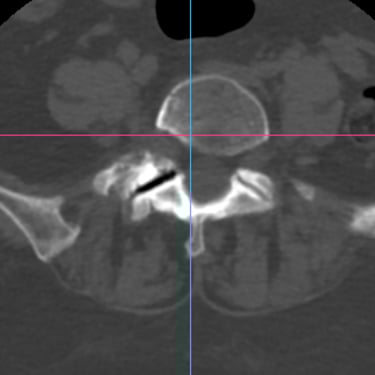

La listesis lumbar L5–S1 es una afección en la que una vértebra se desliza sobre otra, provocando inestabilidad, dolor lumbar y, en muchos casos, compresión de las raíces nerviosas. Cuando el tratamiento conservador no logra controlar los síntomas, la fusión intersomática transforaminal (TLIF) se presenta como una opción quirúrgica efectiva. Este procedimiento permite descomprimir las estructuras nerviosas, restaurar la alineación vertebral y lograr una fijación sólida mediante tornillos transpediculares e injerto óseo. La técnica TLIF reduce el dolor, mejora la estabilidad de la columna y favorece una recuperación funcional progresiva y segura.